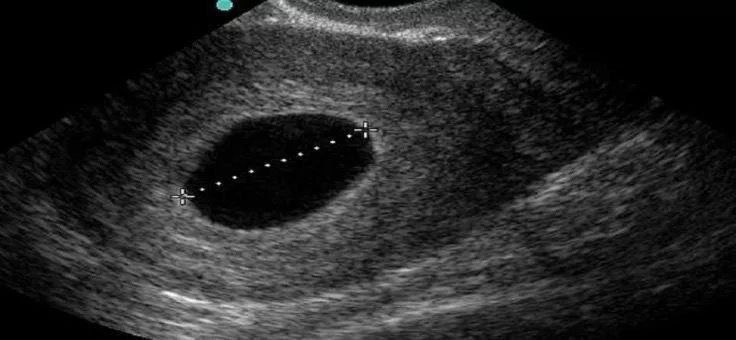

Пациентка обратилась в больницу с задержкой менструального цикла. Ультразвуковая диагностика помогла обнаружить плодное яйцо, однако эмбрион в нём отсутствовал. Диагноз — анэмбриония, так называется неразвивающаяся беременность по типу пустого плодного яйца.

Фото: Минздрав Ставрополья.